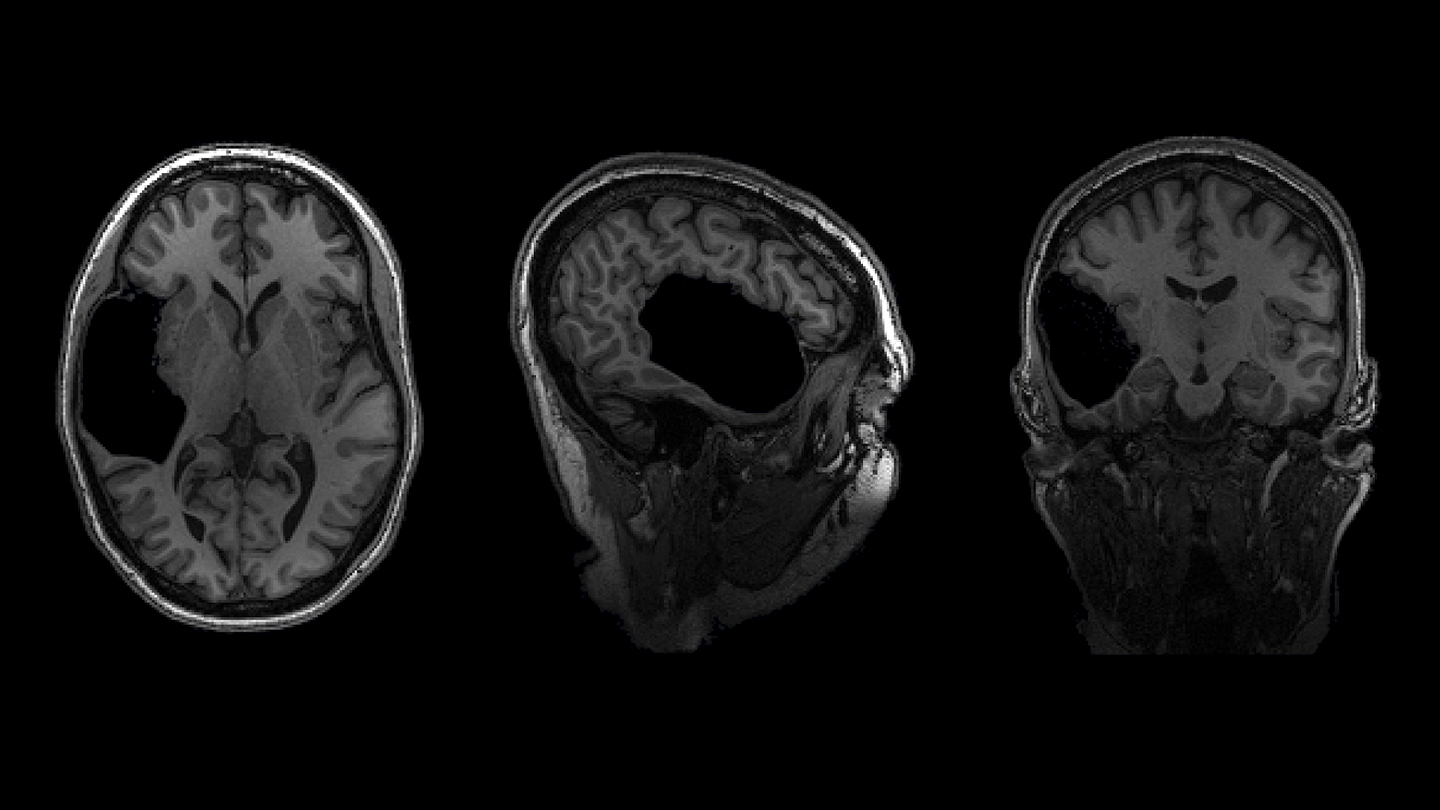

А вот при взгляде на снимки ее мозга - совсем другое дело. Такое впечатление, что кто-то опрокинул бутылку с чернилами. Внутри черепа, возле левого уха, образовалась лужица черных чернил. Внутри пятна нет ни белого, ни серого вещества, ни кровеносных сосудов, ни тканей.

Ученые не могут точно сказать, как это произошло. Возможно, когда-то давно, возможно, в результате инсульта, случившегося до или вскоре после рождения, часть мозга Элизы умерла и в конце концов исчезла, оставив после себя только жидкость - ткани мозга заменила заполненная жидкостью пустота. У ее сестры тоже есть такая пустота.

Элайза и ее сестра Марта М., которые не называют своих полных имен, чтобы сохранить анонимность, выглядят и ведут себя совершенно обычно. Но у каждой из них отсутствует большая часть височной доли, причем в разных полушариях. У Элизы также отсутствует часть ствола мозга. Эти женщины - две из тех, кто знает, сколько людей прожили свою жизнь без структур мозга, которые обычно считаются важнейшими.

У Марты М., младшей сестры Элизы Г., также отсутствует большая часть височной доли, но на правой стороне мозга - почти зеркальное отражение поражения Элизы. Возможно, Марта перенесла инсульт еще в утробе матери. Позже скопление жидкости в мозге давило на нервы ее глаз, что мешало ей видеть. Как и у всех участников проекта "Интересный мозг", у Марты по языковым и когнитивным задачам средний балл или выше среднего.

Первое сканирование Элизы, проведенное командой Федоренко, выявило языковую активность в правой части мозга, о чем команда сообщила в 2022 году в журнале Neuropsychologia. По словам Федоренко, смещение функций вправо - это один из приемов, с помощью которого наш мозг справляется с повреждениями в левой части, о чем ранее сообщали другие ученые.

Но в этой доле вообще не было обнаружено зон, реагирующих на язык. Полученные результаты указывают на нейронный порядок действий при развитии языка: Без левой височной доли Элизы языковые зоны в ее левой лобной доле не могли подключиться.

Команда Федоренко также обнаружила, что у Элизы полностью отсутствует типичная область для чтения слов. Команда полагала, что такая область может проявляться в правой височной доле Элизы. Вместо этого, как оказалось, она использует сеть нейронов в зрительной коре, о чем команда сообщила в этом году в журнале Cognitive Neuropsychology.